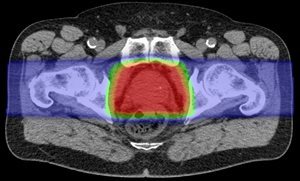

Prostate Cancer Treatment Scca Proton Therapy Center

Proton Therapy For Prostate Cancer

Proton Therapy For Prostate Cancer Texas Center For Proton